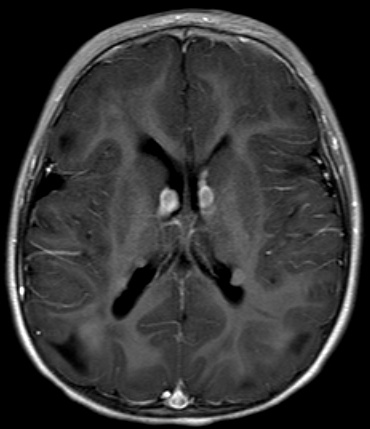

A 3-year-old boy is brought to the clinic due to increased seizure frequency.  Over the past year, the patient has had recurrent tonic-clonic seizures that are poorly controlled despite multiple antiepileptic medications.  The seizures have become more frequent in the past month and now occur daily.  The patient has developmental delay and receives speech and physical therapy.  He was born at term without perinatal complications and has received all age-appropriate vaccinations.  Family history includes mild intellectual disability in his father.  Physical examination is notable for multiple 1- to 2-cm hypopigmented macules on the trunk and lower extremities.  MRI of the brain reveals subependymal nodules, as shown in the image below: A 3-year-old boy is brought to the clinic due to increased seizure frequency.  Over the past year, the patient has had recurrent tonic-clonic seizures that are poorly controlled despite multiple antiepileptic medications.  The seizures have become more frequent in the past month and now occur daily.  The patient has developmental delay and receives speech and physical therapy.  He was born at term without perinatal complications and has received all age-appropriate vaccinations.  Family history includes mild intellectual disability in his father.  Physical examination is notable for multiple 1- to 2-cm hypopigmented macules on the trunk and lower extremities.  MRI of the brain reveals subependymal nodules, as shown in the image below:   Which of the following is associated with the most likely underlying condition in this patient? A) Cardiac rhabdomyoma B) Optic nerve glioma C) Pheochromocytoma D) Vestibular schwannoma E) Wilms tumor (nephroblastoma) Which of the following is associated with the most likely underlying condition in this patient?